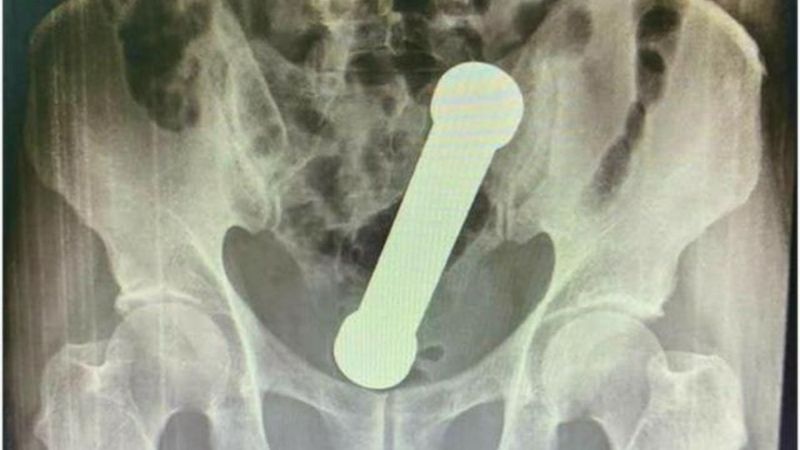

Röntgende görüldü

Hastaneye karın ağrısı şikayetiyle başvurarak doktorlara nedenini söylemeyen hasta, röntgen sonucunda içerideki dambılı gördü.